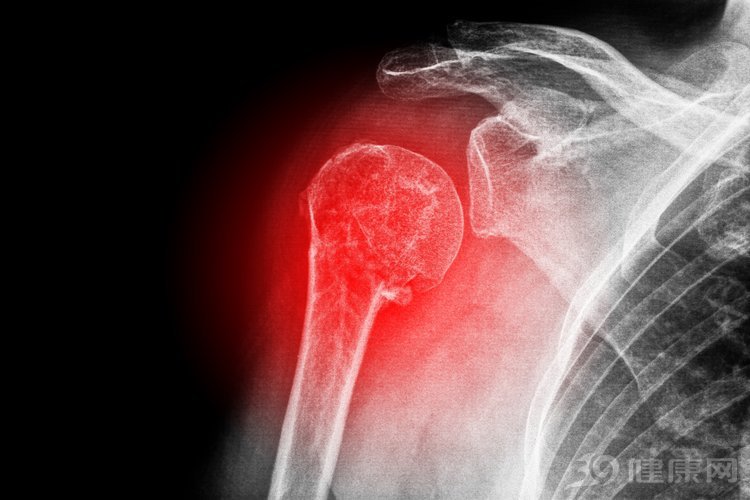

骨转移是指癌症从身体的另一部分开始并扩散到骨骼。它有时被称为继发性骨癌或转移性骨病,骨转移与从骨中开始的癌症(称为原发性骨癌)不同。骨转移比原发性骨癌更常见,某些类型的癌症更容易传播到骨骼,例如乳腺癌、前列腺癌、肺癌、肾癌等。

骨转移的症状取决于受影响的骨骼和骨骼的数量。骨转移通常是第一个症状是骨骼疼痛。骨痛可以是转移性的,也可以是固定的。晚上往往疼得更厉害。骨转移的疼痛是一种钝痛或剧烈疼痛。

由于癌症骨转移会导致骨质便成游离状态,骨质当中缺乏钙离子,从而导致骨头脆性增加,骨折就是这样出现了,最常见的是肋骨,椎骨和腿骨。